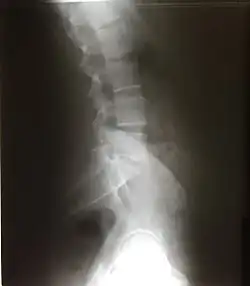

Lateral lumbar X-ray of a 34-year-old male

The lumbar curve is more marked in the female than in the male; it begins at the middle of the last thoracic vertebra, and ends at the sacrovertebral angle. It is convex anteriorly, the convexity of the lower three vertebrae being much greater than that of the upper two. This curve is described as a lordotic curve.